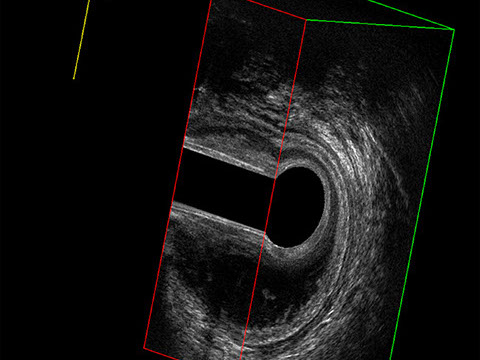

Proctal dispone di apparecchiatura per ecografia endoanale 3D con sonda rotante.

Sezione Longitudinale 3D con Tramite Fistoloso Intersfinterico Basso Anteriore Semplice